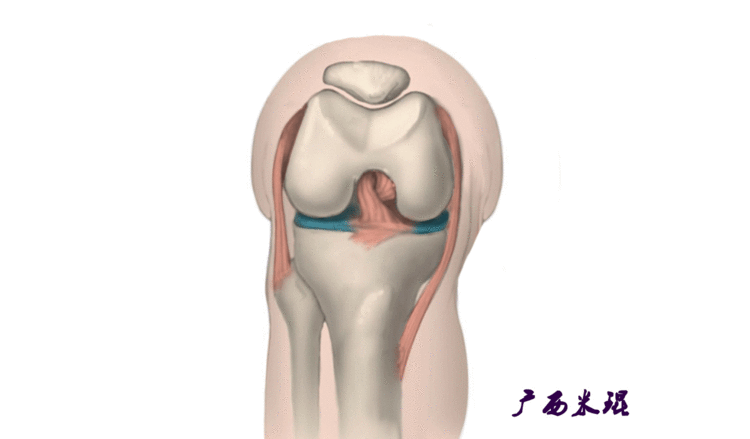

说到髌骨脱位,首先就要了解髌骨,髌骨是人体最大的籽骨,倒三角状位于膝关节前方,它的上缘与股四头肌腱相连,下缘通过髌韧带止于胫骨结节上,两侧为股四头肌扩张部,髌骨后方的凸面为光滑的关节面,与股骨下端内外髁之间的滑车凹面关节面形成关节。尽管股四头肌中的股直肌、股中间肌、股外侧肌的作用方向与髌韧带不在一条直线上,髌骨有向外突出的倾向,但因股内侧肌有向内上方牵拉作用力而使髌骨维持在正常位置。